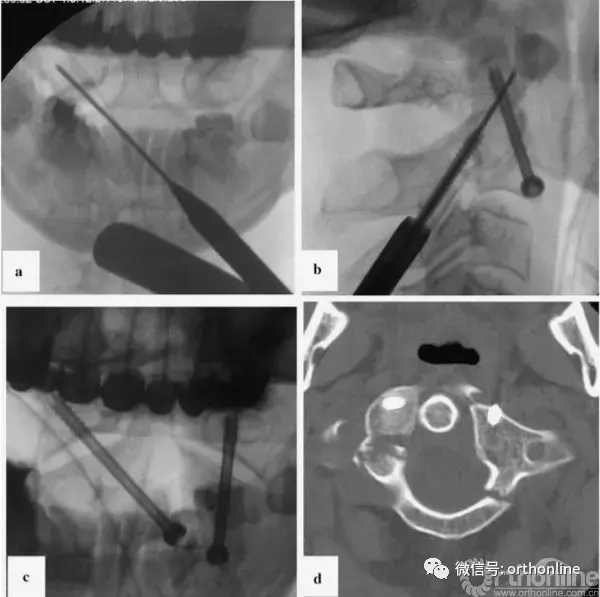

图4

图4案例2术后x线影像及CT扫描;a、开口位的x光片;b、侧位x光片,我们继续观察到寰枢关节复合体的背脱位高达4毫米;c、C2椎体螺钉位置;d、螺钉在C1椎体的位置;CT,计算机断层扫描

Fig. 4 Case 2: post-operative X-ray images and CT scans. a Control X-ray in the transoral plane. b Control X-ray in the lateral plane. We continued to observe dorsal dislocation of the atlantoaxial complex by up to 4 mm. c Screw position in C2 vertebra. d Screw position in C1 vertebra. CT computed tomography